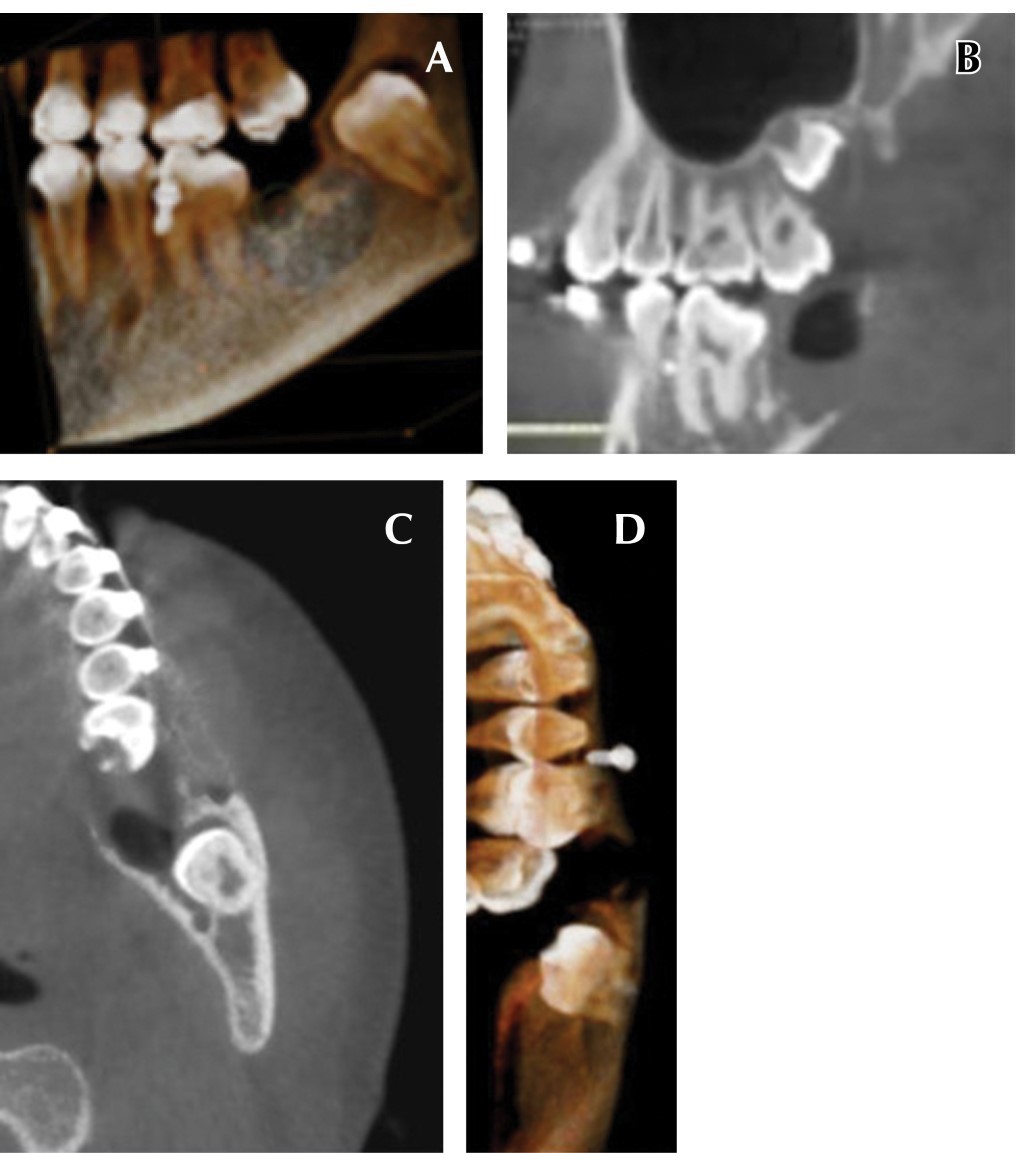

La radiografía panorámica permitió observar un área radiolúcida unilocular que se extendía a partir del cuerpo mandibular (Figura 1), desde la zona distal del primer molar inferior izquierdo hasta la parte mesial del segundo molar incluido, involucrando el canal del nervio inferior. El segundo molar inferior estaba incluido en la lesión y desplazado posterosuperiormente, así como desplazamiento basal del conducto dentario inferior. En la tomografía axial computarizada con reconstrucción se apreció una masa isodensa en el cuerpo y rama mandibular izquierda, con expansión de corticales vestibular y lingual (Figura 2).

Bajo anestesia general y con intubación orotraqueal, se realizó la resección quirúrgica conservadora de la lesión, con curetaje en todo el lecho quirúrgico y odontectomía del segundo molar inferior izquierdo. No se observó comunicación al conducto dentario inferior ni perforación de las corticales óseas en el transoperatorio (Figura 3).